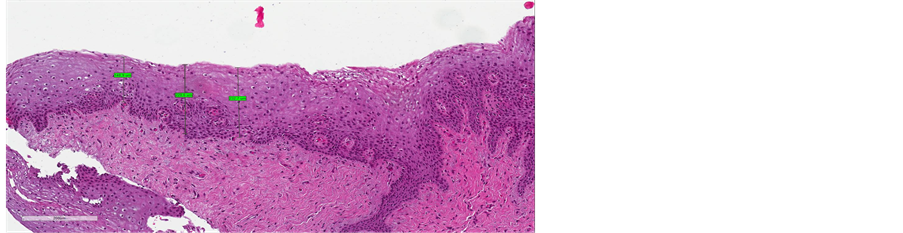

Before treatment, the stratified squamous epithelium appeared atrophic and thin, with no evidence of the crests of the Malpighian layer and epithelial papillae, and with a flattened sub-epithelial junction (Figure 4(a), Figure 5(a), Figure 6(a)). Post-treatment histology samples showed restoration of the epithelial and subepithelial structures, characteristic of reproductive-age vaginal mucosa

(Figure 4(b), Figure 5(b), Figure 6(b)). Immunostaining for collagen III and IV demonstrated a visible post-treatment enhancement. Microscopic examination of the biopsy sections revealed a striking increase in the thickness of epitelium, with resurfacing of the Malpighian layer and epithelial papillae. The median improvement from baseline in epithelium thickness was 97% (range: 9% - 203%).

Figure 6. (a) pre-treatment measure (from minimum measure 148 µm to maximum measure of 232 µm); (b) post-treatment measures (from minimum measure of 416 µm to maximum measure of 482 µm).